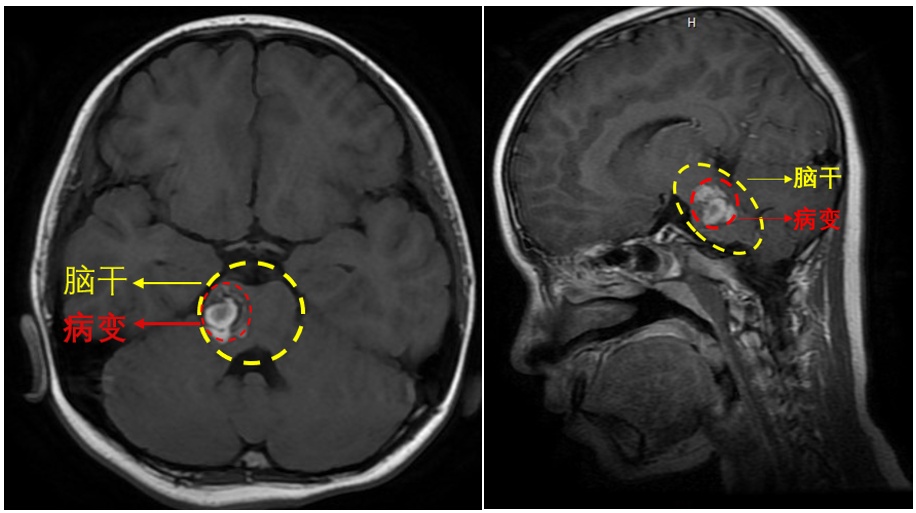

脑干(如下图所示)是大脑的核心区域,同时又因其周围密布神经,既往常被称为手术的禁区,脑干为生命中枢部位,脑干出血病情严重,可以引起昏迷不醒甚至危及生命等,这个部位是人体最脆弱的地方,脑干病变致残致死率高,手术治疗极具有挑战性。

那么是什么原因导致了小琪罹患了致命疾病?原来是一种叫海绵状血管瘤的东西,长在了小琪的脑干右侧,即右侧桥脑部位。

脑桥,又称桥脑,是脑干的一部分。位于延髓和中脑之间,前、后缘有横沟分界。脑桥的腹侧面积脑桥基底,内有大量的横行纤维,连接小脑半球,也有一些纵行的神经纤维。自脑桥出入的脑神经有三叉神经、展神经、面神经和前庭蜗神经,控制着人体大部分的感觉和运动功能,尤其还包括与呼吸相关的调节中枢。